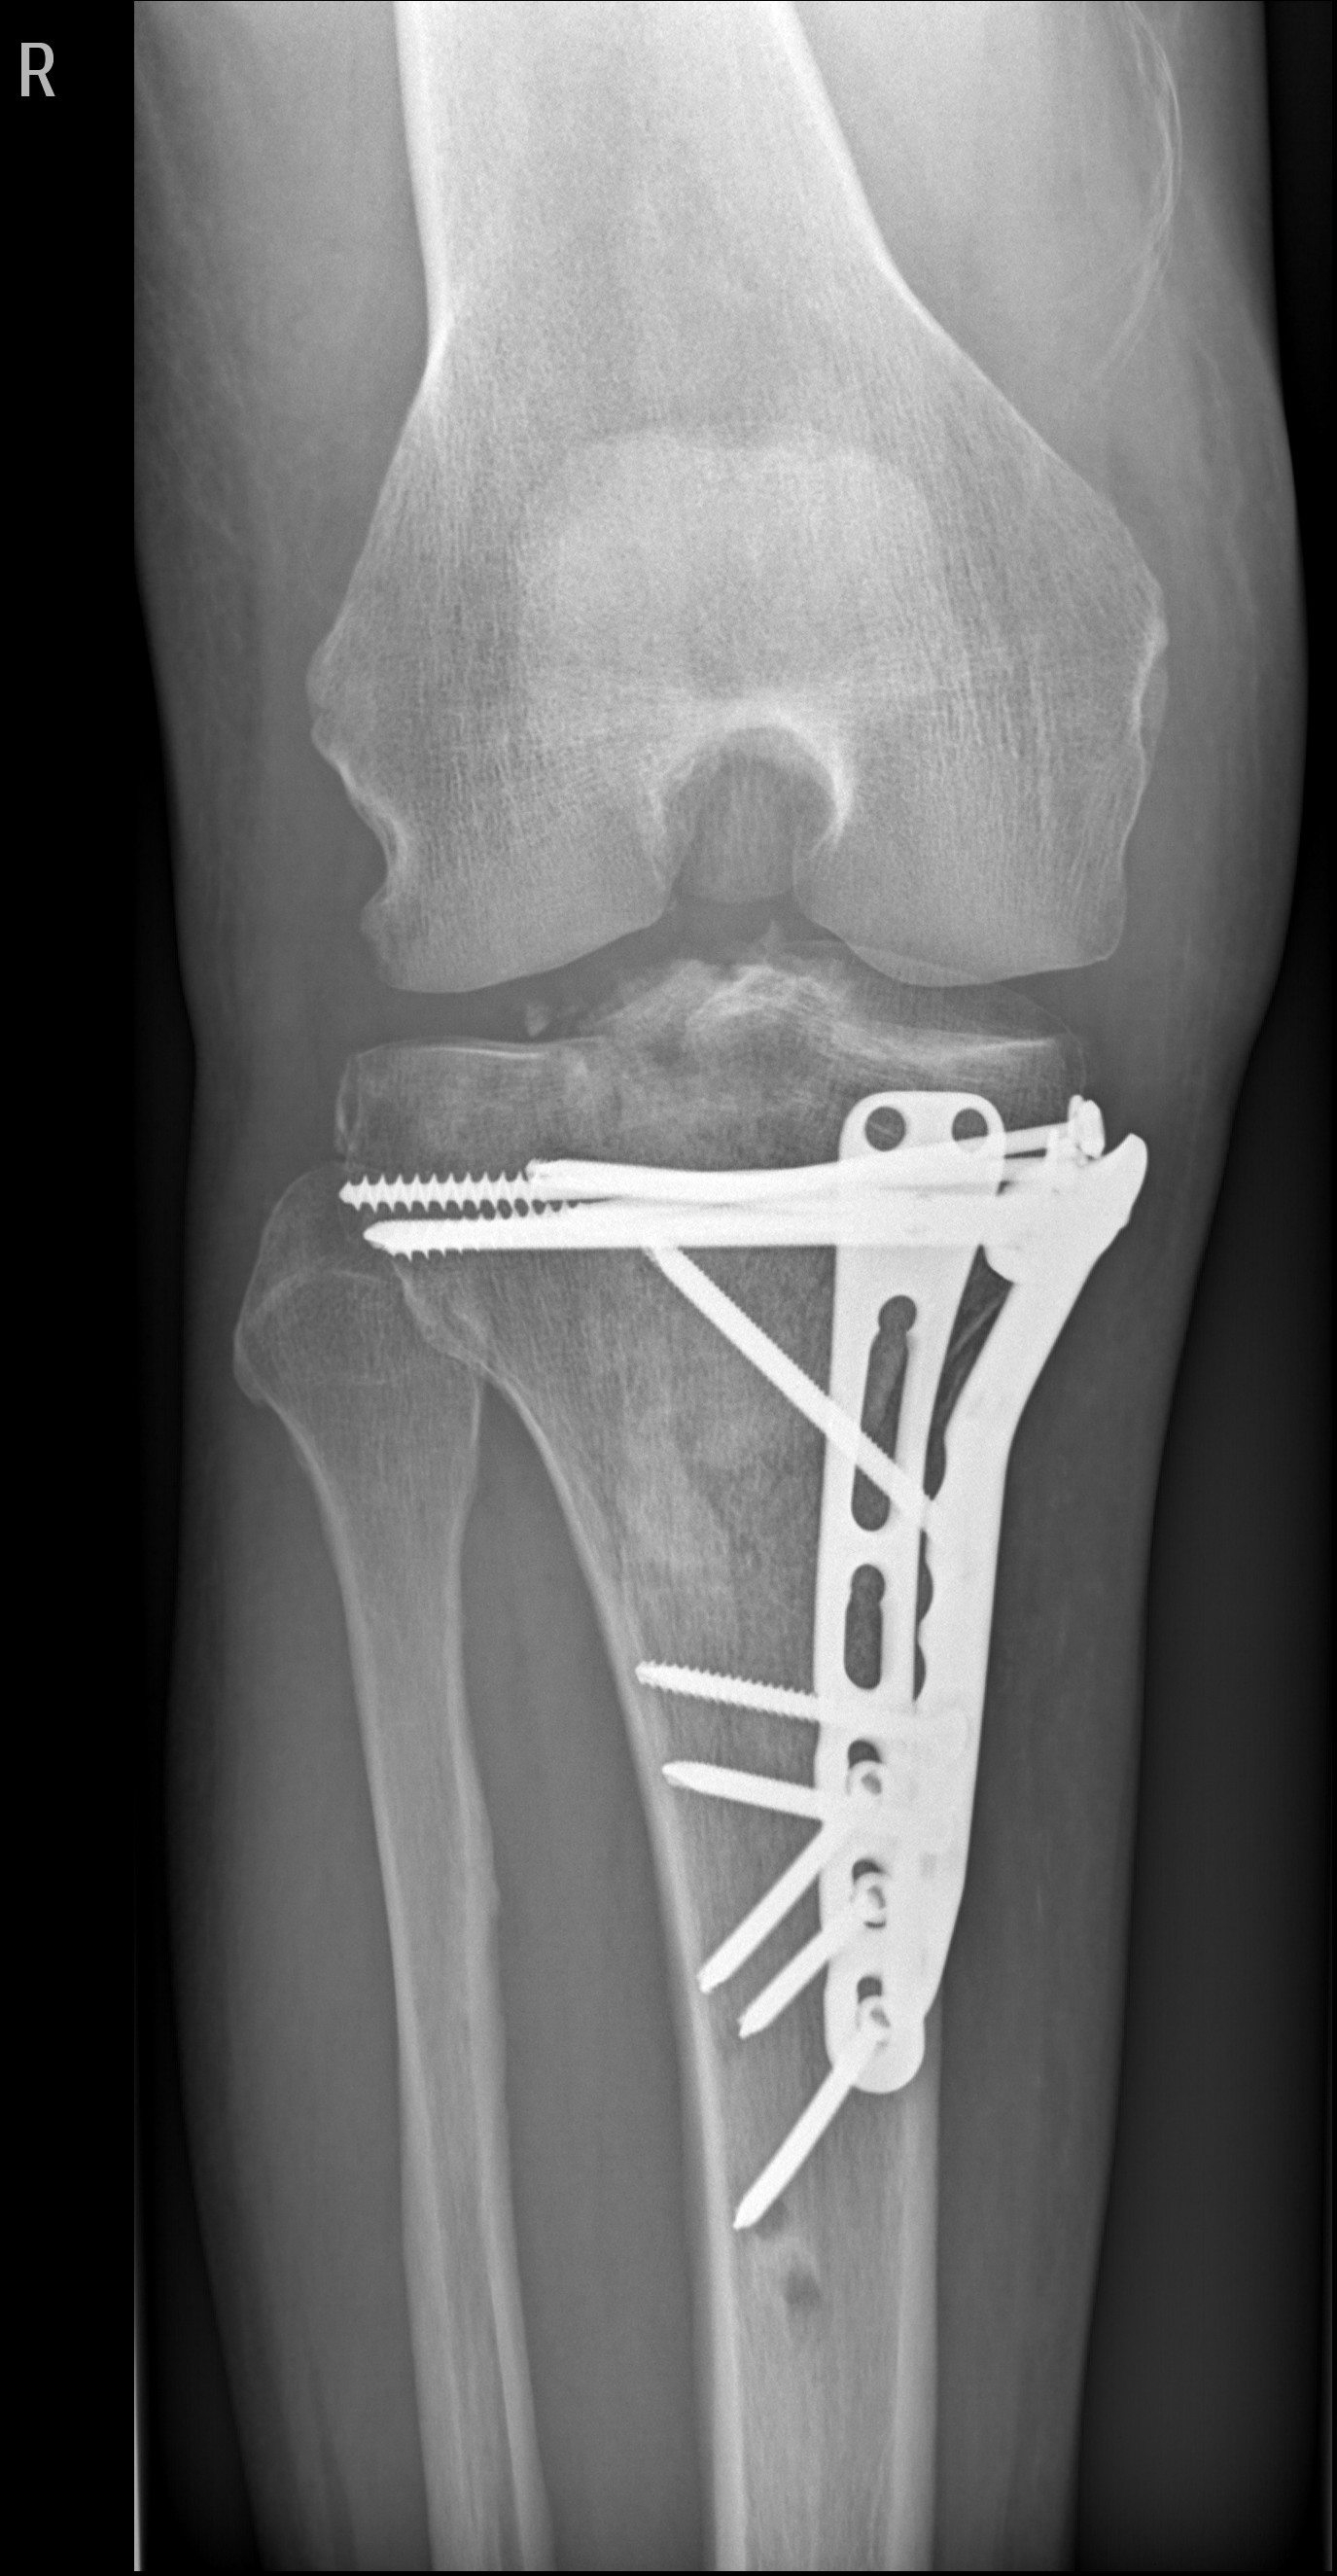

Anhang anzeigen 567019Anhang anzeigen 567020

15-04-2022

Anhang anzeigen 567021

Schrauben noch fest

12-01-2023

Anhang anzeigen 567023Anhang anzeigen 567024

Schrauben raus, geplante Vollprothese Mitte/Ende Dezember 2023, denkbar geheilt, 04-2024. Dann werden es 3 Jahre gewesen sein![]()